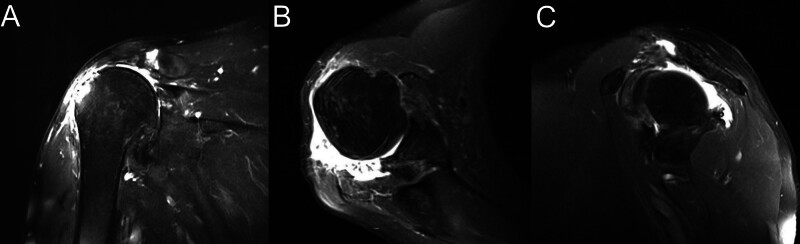

Diagnoses: Massive IRCT of supraspinatus, infraspinatus, and subscapularis with retraction (Goutallier grade 3, Hamada 4b); 4-cm retracted middle deltoid tear; rotator cuff tear arthropathy with superior humeral head migration, acromial sclerosis, and glenohumeral degeneration, confirmed by x-ray, computed tomography, and magnetic resonance imaging. Preoperative Constant-Murley score: 27 (pain: 2, activities of daily living: 10, movement: 12, strength: 2).